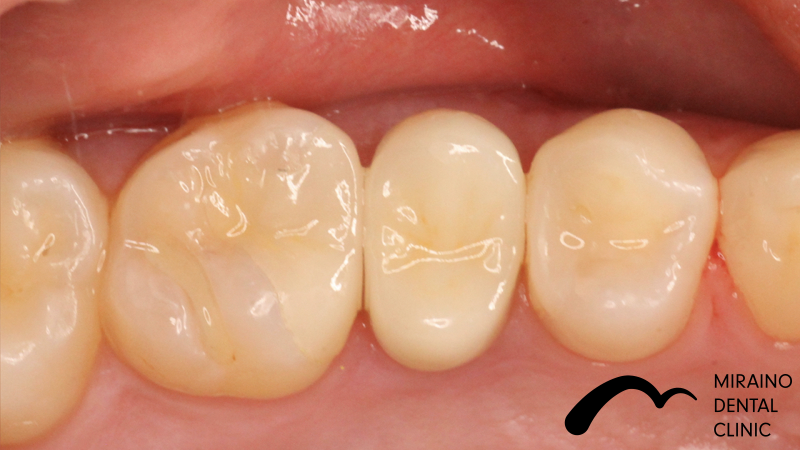

詰め物・メタルフリーインレーの症例

Case2

| 施術名 | 詰め物・メタルフリーインレー |

| 施術の概要 | 定期検診の際に、5年前以上に治療した銀歯に伱間があることを衛生士が見つけました。 沁みる、噛むと痛いといった症状はありませんでしたが、 次回再発した際は神経を取らないといけなくなる可能性が高いため、 なるべく再発しにくい歯科治療を希望され、メタルフリーインレーによる修復治療を行いました。 |

クリックして詳細を表示

| 施術の内容 | 銀歯は歯より硬すぎる、歯を腐食させる作用があることから約5年で再発すると言われています。 ラバーダムを用いて唾液による接着不良のリスクを排除し完全に水分を排除した状態でムシ歯治療を行います。 型取りを行い、技工士によって汚れの付きにくいセラミックで形を再現している。 |

| 1歯あたりの治療費 | 1歯:50,000円 |